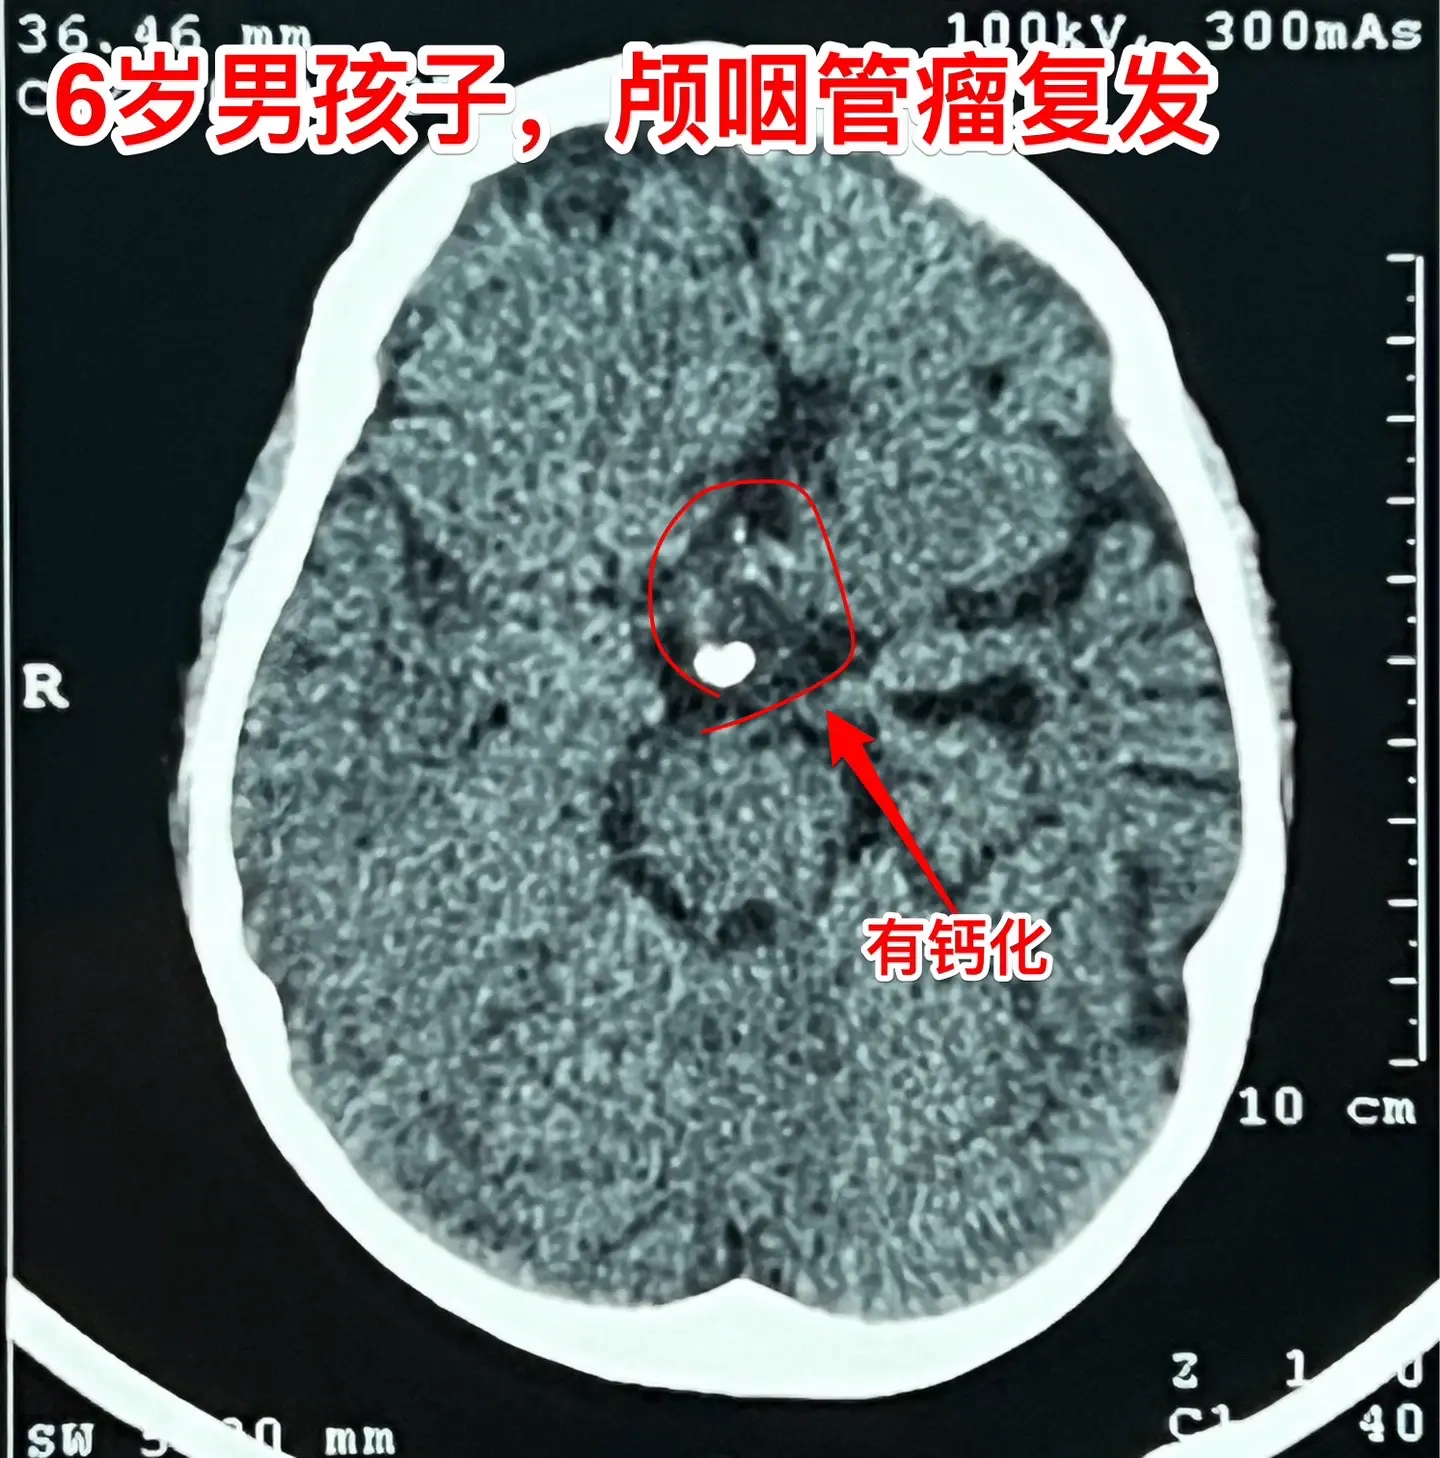

今日两个颅咽管瘤手术。1,6岁男孩子,安徽宿州人。2023年5月因视力下降发现了脑部长了巨大颅咽管瘤,见图1。家长曾经通过微信找我看过,最终选择在上海某医院行手术治疗,手术后出现右侧偏瘫,经过康复治疗后能勉强走路,但是右手还不能拿笔写字。2023.12磁共振就显示颅咽管瘤复发了(多块肿瘤复发)。2024.10又出现视力下降,故来找我作手术。今天手术中发现有四块较大的肿瘤,同时有很多个小钙化。所见肿瘤均顺利切除了。对比两次手术前的磁共振,可以说第一次手术更容易达到完全切除肿瘤,很遗憾,那一次机会错过了。 2,9岁男孩子,江苏盐城市的。因头痛、呕吐检查发现脑部有典型的颅咽管瘤,伴有脑积水。病人到我科住院后经用甘露醇和地塞米松后头痛、呕吐症状消失,能正常吃喝。今日作了开颅手术,顺利切除肿瘤。